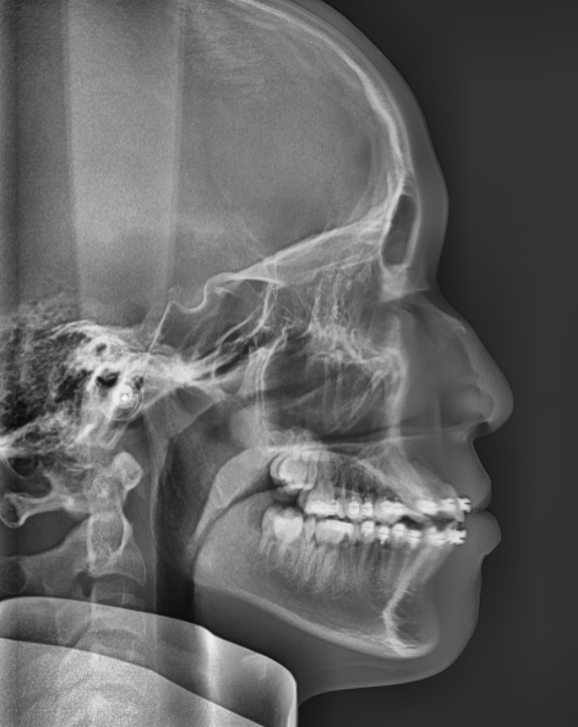

class III ceph.JPG